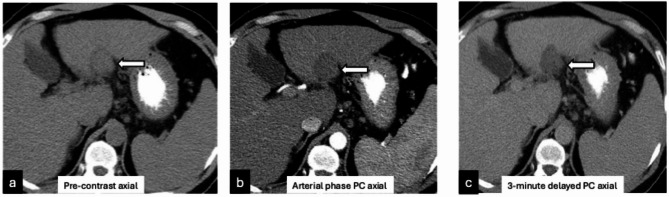

背景:通过肝移植前横断面成像准确评估肝细胞癌存活情况对于肝移植后正确的器官分配和患者的整体预后非常重要。目的:通过对比增强多期CT和MRI,确定LI-RADS TRA与外植体病理在热消融患者中的准确性。材料和方法:由三名委员会认证的放射科医生对2001年3月至2019年9月在一家三级医院接受热消融和肝移植治疗的119例连续成人HCC患者的影像学研究进行回顾性研究。将每个肿瘤的LI-RADS TRA分类与外植体病理进行比较。采用Cohens Kappa检验和Fleiss κ检验,95%置信区间采用bootstrap技术。结果:经皮热消融治疗的119例hcc患者(中位年龄59岁,男性95例[80%])中,68%完全坏死,32%病理存活。在外植体上存活的肿瘤在治疗前成像时较大(中位数为2.4 vs. 2.1 cm;P = 0.02),组间移植前消融腔大小无差异(分别为4.0和3.9 cm;p = 0.58)。LI-RADS TRA对存活肿瘤的NPV为71% (68-74);PPV为62.5% (39 ~ 81)(p = 0.01),敏感性为19%(9.4 ~ 32),特异性为95%(89 ~ 98),准确性为70%(63 ~ 77)。在外植体上,33例患者中发现55例意外治疗naïve移植前成像不可见的存活肿瘤。结论:即使应用于相对均匀的经皮消融队列,LI-RADS TRA的“不可存活”类别在预测肿瘤缺失方面也表现出较低的敏感性。与外植体病理相比,MRI在预测肿瘤生存能力方面比CT更准确。

Results: Of the 119 patients (median age 59 years, 95 [80%] male) with 165 HCCs treated with percutaneous thermal ablation, 68% were completely necrotic and 32% were viable on pathologic analysis. Tumors viable on explant were larger on pre-treatment imaging (median 2.4 vs. 2.1 cm; p = 0.02) with no difference in pre-transplant ablation cavity sizes between groups (4.0 vs. 3.9 cm, respectively; p = 0.58). NPV of LI-RADS TRA for viable tumor was 71% (68-74); PPV of 62.5% (39-81) (p = 0.01) with a sensitivity of 19% (9.4-32), specificity of 95% (89-98), and accuracy of 70% (63-77). On explant, 55 incidental treatment naïve viable tumors, not visible on pre-transplant imaging, were found in 33 patients.

Conclusion: The "non-viable" category of LI-RADS TRA even when applied to a relatively uniform percutaneous ablation cohort, demonstrated low sensitivity in predicting absence of viable tumor. MRI had more accuracy than CT in predicting tumor viability when compared to explant pathology.